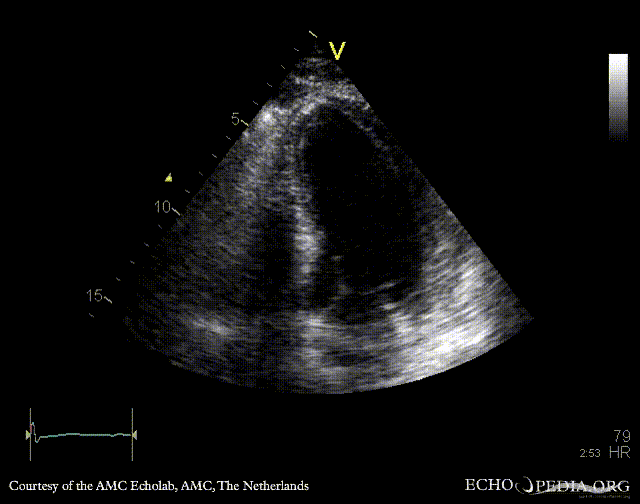

A3CH: akinesia of basal posterior wall A4CH: strain image

E00522.jpg

E00523.jpg

A2CH: strain image A3CH: strain image